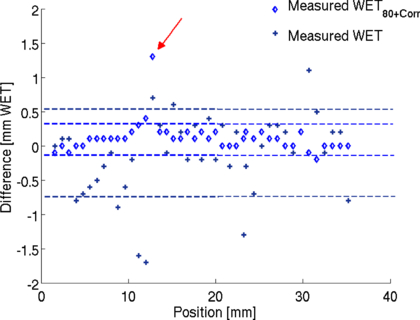

For validation of the energy scan method the WET distribution of a cylindrical PMMA phantom was measured. The signal as a function of the applied beam energy was obtained for each detector pixel. An example of such a curve is shown in figure 4. The obtained peak position corresponds to a certain initial beam energy Einit, max. It is translated into its corresponding water equivalent range (WET). The measured WET values are then given by the subtraction of the WETFlat-panel. They agree well with the expectation from the calculation (see figure 5(a)). The measured WET resolution is limited by the energy steps available from the accelerator. Due to the very different measured peak shapes it is not possible to fit for example a learning base-data set to the obtained signal curve to increase WET resolution. However, a possible way to increased WET resolution is by linear interpolation of the energy-signal curve and evaluation of S80 at which the signal amounts to 80% of the peak value at the steep descending flank of the peak, see figure 4. This idea is based on the fact that the descending flank is very steep and similar for all signal-energy curves. The WET80 value obtained at 80% of the signal increases WET resolution as seen in figure 5(b). However, the measured values are slightly lower than the calculated values. This underestimation can be quantified by investigation of the energy-signal correlation. When passing through matter, an ion experiences deflection caused by the Coulomb field of the nucleus. Neglecting multiple Coulomb scattering in homogeneous material, initial beam energy variation only shifts the Bragg peak in depth while preserving the peak shape. Therefore, the shift between the Smax and S80 value is nearly constant and can be used as a correction factor. Figure 5(b) shows the corrected WET80 values. They agree very well with the calculation. The standard deviations between the calculated and measured WET values are given in figure 6 indicated by the dashed lines. With the interpolation method the standard deviation decreases from 0.61 mm WET to 0.22 mm WET. However in the case of more complex imaging objects, the Bragg peak degrades due to multiple Coulomb scattering at material interfaces (Urie et al 1986). This Bragg peak degradation leads to an increased peak width; see figure 7. As a result the S80 is shifted here towards higher energy values. Correspondingly, the initial beam energy Einit, 80 is shifted to higher energies, which corresponds to smaller WET80 values. The effect of Bragg peak degradation is strongly correlated to the local inhomogeneity of the imaged object. For the WET measurement of our cylindrical PMMA phantom, minor Bragg peak degradation due to particle scattering and partial volume effect can explain the slight underestimation of measured WET value at the location of around 13 mm, indicated by the red arrow in figure 6.

Standard imageFigure 6. Difference between calculated and measured WET values. Lines indicate one standard deviation. Larger deviation occurs at a position of around 13 mm indicated by the red arrow.

Download figure: